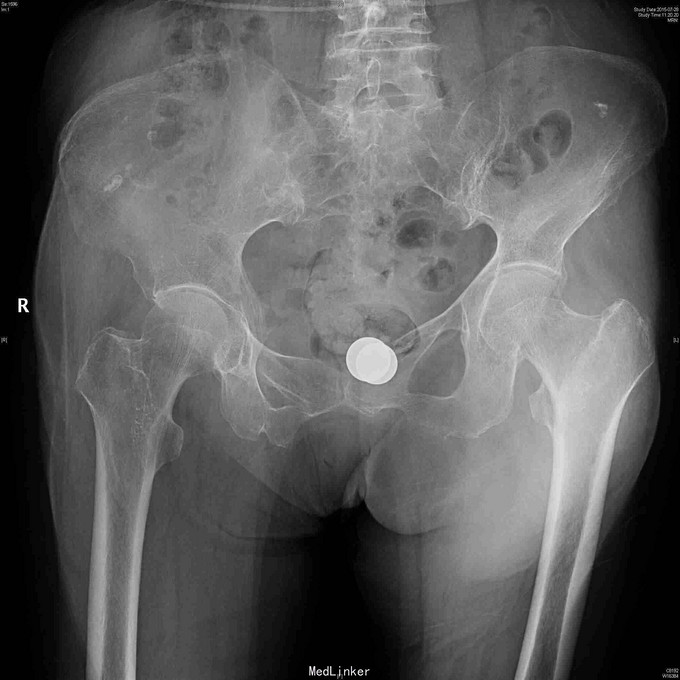

82岁女性,摔倒致左髋疼痛,短缩外旋畸形5小时。

查体:左下肢轻度外旋短缩,左髋大转子叩痛,轴向叩击痛。 左髋放射片:左股骨粗隆间骨折,轻度移位。